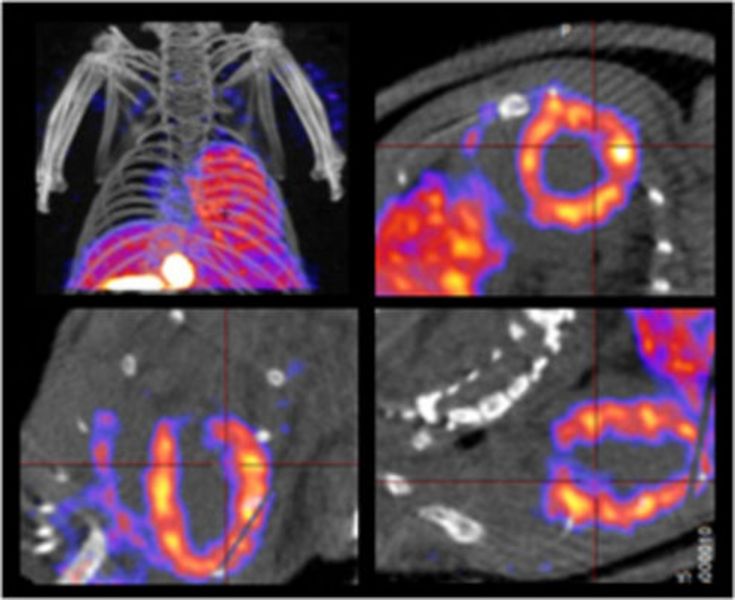

Positron emission tomography is a highly sensitive, quantitative imaging modality being capable of assessing molecular dynamics in vivo with nano-/picomolar sensitivity. The PET methodology available within the core unit is a dedicated high resolution small animal PET scanner with sub-milliliter resolution and a large field of view (28 cm * 16 cm). This camera is one of only four installations worldwide (quadHIDAC, Oxford Positrons Ltd., Oxford, UK). Due to cooperations with the Department of Nuclear Medicine and the Collaborative Research Center SFB 656 MoBil “Molecular Cardiovascular Imaging” at the University of Münster, this core unit is able to offer a wide range of different molecular imaging probes ranging from whole-body measurement of perfusion and metabolism down to cell imaging and imaging of targets being involved in oncological, inflammatory, neurological, cardiovascular and other diseases.Small Animal Computed Tomography (CT)

Computed tomography is an anatomic imaging modality with a very high spatial resolution. In the core unit group, this method is used primarily to provide anatomical information in correlation to the distribution of specific molecular imaging probes in PET and SPECT. In general, small animal CT alone offers a spectrum of applications similar to CT in the clinical setting.Integrated Small Animal PET/MRI